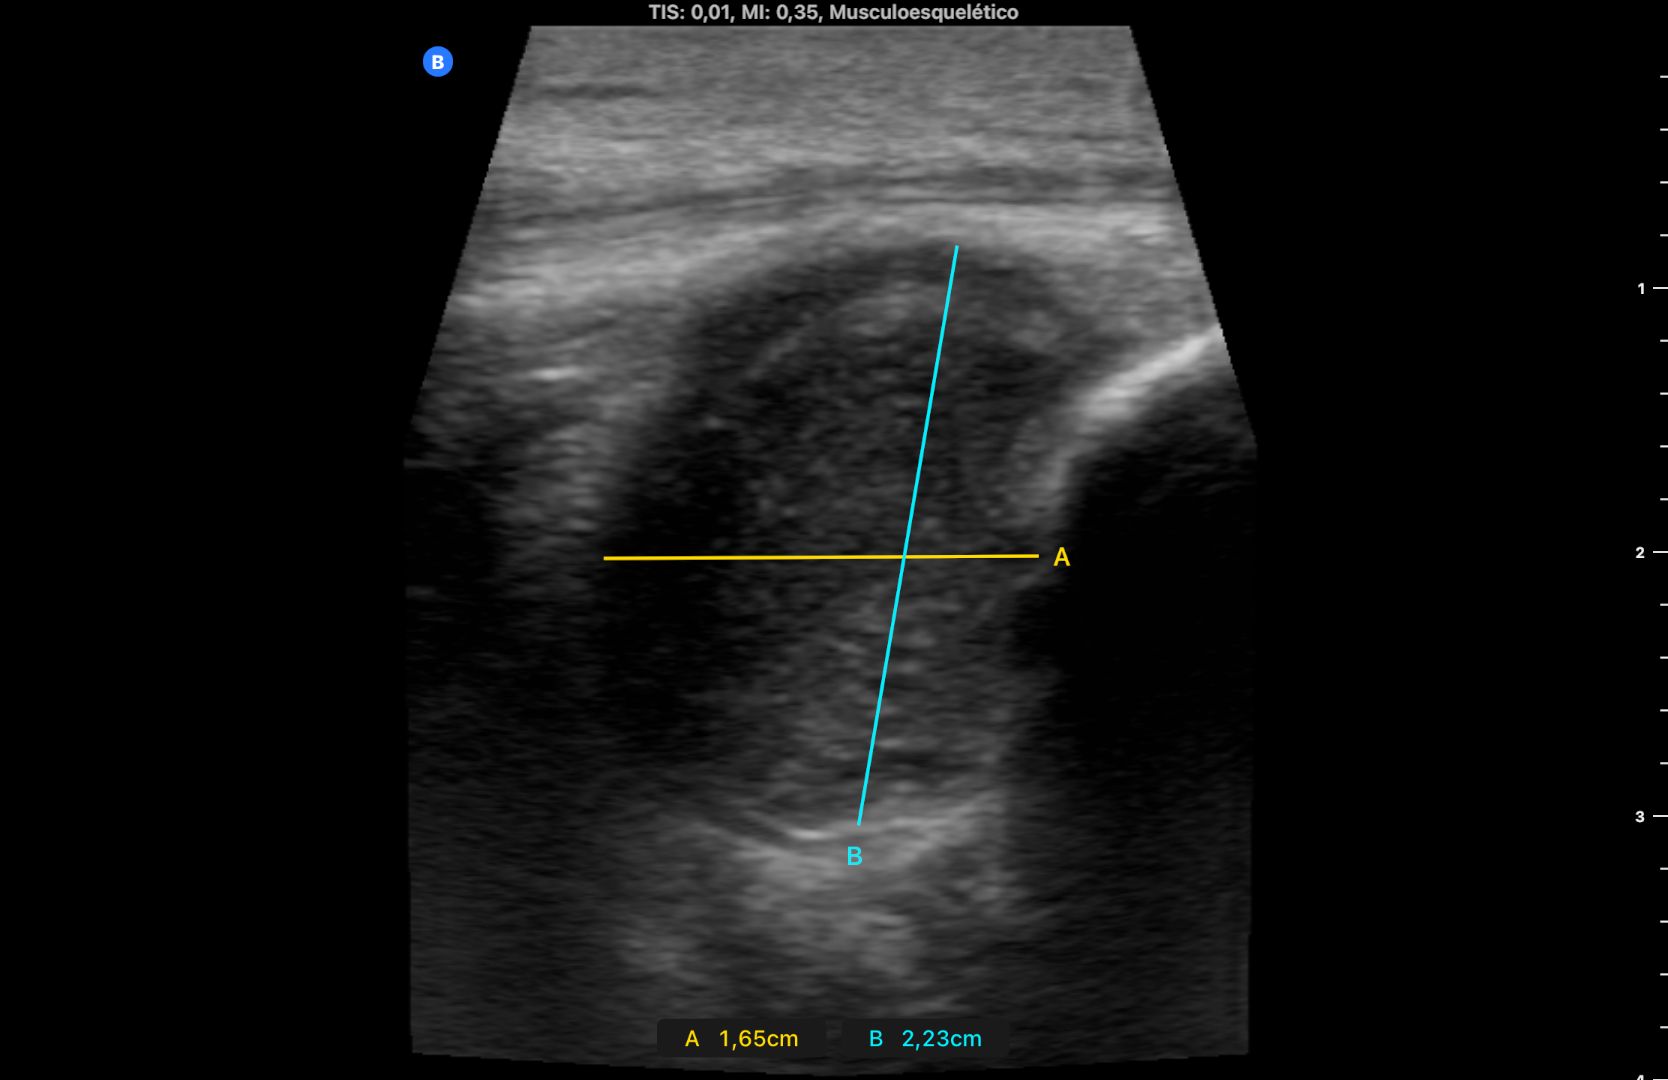

En RMN plantean tumor de células gigantes versus artropatía gotosa tofácea (imagen 2).

Se revisa la historia clínica y se solicita analítica. En un episodio cerrado consta que hace 12 años el paciente presentó un primer cuadro de hiperuricemia sintomática (ácido úrico 10,6) y en una ecografía de rodilla se visualizó derrame articular con ligero engrosamiento sinovial compatible con artropatía gotosa; se inició Alopurinol y el ácido úrico disminuyó a 6. Cuatro años después el paciente cesó el tratamiento por su cuenta. En la analítica actual presenta ácido úrico de 11,6 y se reintroduce Alopurinol. El TAC espectral muestra aumento de partes blandas compatible con tofo gotoso y el análisis espectral de descompresión de materiales muestra depósitos de ácido úrico. La RMN multiparamétrica describe hallazgos compatibles con artropatía tofácea crónica.